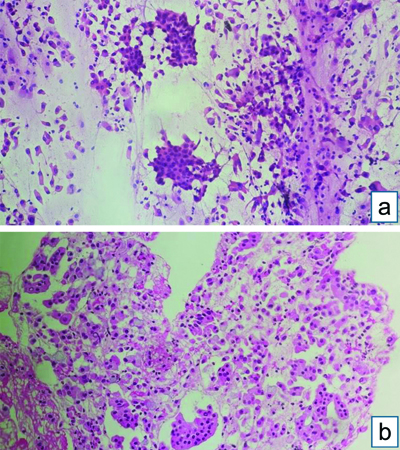

Endobronchial Ultrasound-guided Transbronchial Needle Aspiration (EBUS-TBNA) with a total of 7 passes was done. The aspirate and bronchial wash were reported as suspicious for malignant cells [Table/Fig-4a]. The EBUS-TBNA core [Table/Fig-4b] and endobronchial biopsies were received as multiple very tiny grey-white to grey-brown soft-tissue bits altogether aggregating to 0.5 cc. Histopathological analysis of the endobronchial biopsy [Table/Fig-5] revealed the diagnosis of lung adenocarcinoma with SRC morphology characterised by abundant intracellular mucin accumulation and a crescentic nucleus displaced toward one end of the cell. This was confirmed by IHC, the tumour cells showed positivity for markers CK7 [Table/Fig-6] and TTF-1 [Table/Fig-7]. Further, the tumour was positive for ALK [Table/Fig-8] gene rearrangements and negative for ROS proto-oncogene1 (ROS1) fusion by IHC. Epidermal Growth Factor Receptor (EGFR) mutational analysis was done by Polymerase Chain Reaction (PCR) and no mutation of the EGFR gene was detected.

EBUS-TBNA: (a) Aspirate showing cellular smear, atypical cells with mild to moderate nuclear pleomorphism, admixed with bronchial epithelial cells- Suspicious of malignancy (Haematoxylin and Eosin [H&E] stain x100); (b) Core biopsy showing atypical cell clusters, few with intracytoplasmic mucin, along with bronchial epithelial cell nests (H&E stain x100).